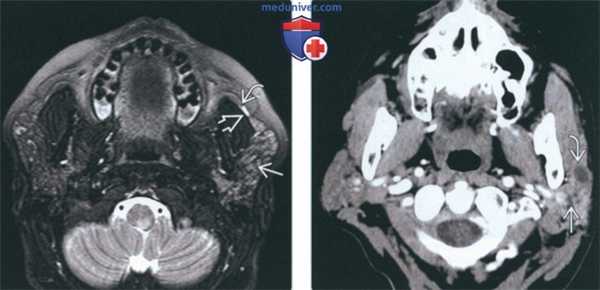

Магнитно-резонансная томография (MRI) выявила наличие подкожного абсцесса левой околоушной области, а также наличие лимфаденопатии с левой стороны (рис. 3) .

Рис. 1. Клинический вид абсцесса околоушной области. Гнойный лимфаденит латеральных шейных лимфатических узлов, появившийся после проведения дистанционной ударно-волновой литотрипсии по поводу лечения предполагаемого сиалолитиаза. Рис. 2. Ортопантомография выявила аномалию прорезывания зуба 38 и наличие фолликулярной кисты.

Рис. 3. Магнитно-резонансная томография выявила формирование подкожного абсцесса в левой околоушно-жевательной области. Рис. 4. При гистологическом анализе участка оболочки удаленной кисты выявлено наличие плотного воспалительного клеточного инфильтрата, состоящего в основном из лимфоцитов и плазматических клеток (окраска гематоксилином и эозином).

(Слева) На традиционной сиалограмме у пациента с паротидным сиаладенитом определяется легкое расширение протоков (реверсивная архитектура). Терминальные протоки и ацинусы практически не визуализируются. В дистальных отделах протока Стенсена определяется рентгенонегативный сиалолит.

(Справа) На корональной КТ с КУ(реконструкция) у семилетнего ребенка с острым вирусным паротитом определяется избыточное контрастное усиление увеличенной правой околоушной железы. Левая железа не изменена. Абсцессы, лимфаденопатия, конкременты отсутствуют.

(Слева) На аксиальной МРТ (STIR) у пациента с острым обструктивным сиаладенитом в левой околоушной железе определяется диффузный сигнал высокой интенсивности относительно правой железы. Главный проток (экстрагландулярный сегмент) справа расширен на фоне обструкции обусловленной маленьким камнем или стенозом.

(Справа) На аксиальной КТ с КУ определяется хронический паротит. Обе околоушные железы атрофированы и имеют слегка неоднородную плотность. Слева определяется расширение интрагландулярного протока и выраженное расширение протока Стенсена. Конкременты не визуализируются.